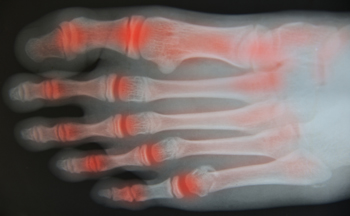

How to Care for Your Arthritic Foot

Arthritis is an inflammation of the joints and it can occur at any joint in the body, especially in the foot. It generally effects those who are older, however, it can occur at any age. Although there are many different forms of arthritis, there are three main types that occur in the foot. The three types are osteoarthritis, rheumatoid arthritis, and gout.

The primary cause of osteoarthritis is aging. As you age, cartilage degenerates around the joints which causes friction and pain. Obesity can cause osteoarthritis through mechanical stress. Injuries that damage joints can increase the probability as well. Finally, a family history of osteoarthritis can also increase chances of having it.

Rheumatoid arthritis occurs when the immune system attacks the joint linings and weakens them over a long time. While there is no known cause of rheumatoid arthritis, obesity and smoking can increase your chances of getting it. Women are also more likely to get it than men.

Gout is a form of arthritis that occurs when there is too much uric acid in your blood and painful crystals form in your joints. Men are more likely to have gout than women. People who are obese or drink alcohol often are also more likely to develop gout. Furthermore, having diabetes, heart disease, high blood pressure, high cholesterol, gastric bypass surgery or a family history of gout may increase your likelihood of developing the condition.

Symptoms of arthritis include pain, stiffness, swelling in the joints. These symptoms can make it harder and more painful to walk. Physical activity can increase pain and discomfort. Furthermore, joint pain can worsen throughout the day for osteoarthritis. Gout attacks generally last several days with the first few being the worst.

Diagnosis of gout includes either a joint fluid test or a blood test. X-ray imaging can detect osteoarthritis but not gout. On the other hand, there is no blood test for osteoarthritis. Rheumatoid arthritis is difficult to diagnosis. Doctors utilize family and personal medical history, a physical examination, and antibody blood tests to determine if you have rheumatoid arthritis.

Treatment varies for the different kinds of arthritis. Anti-inflammatory medication or steroids can help reduce pain from inflammation of the joints. Changing shoe types can help with some symptoms. Wider shoes can help with discomfort from gout and osteoarthritis. High heels should be avoided. Shoes with proper arch support and that take pressure off the ball of the foot can help with rheumatoid arthritis. Drinking lots of water can also help rid uric acid from the blood. Losing weight, improving your diet, and limiting alcohol and smoking can also help prevent or lessen the symptoms of arthritis.

Arthritis Can Affect the Toes

When arthritis develops in the foot, the toes are the most often affected. Arthritis is defined as chronic inflammation that is often accompanied by tenderness, swelling, stiffness, and pain. Toe arthritis is caused by gradual wear and tear of the cartilage. This is what cushions the bones that surround the joints, and is found in two forms of arthritis. Osteoarthritis (OA) is a common form of this condition, in addition to rheumatoid arthritis (RA), which is an autoimmune disease. The bottom of the big toe can become sore with arthritis, and may become worse while walking and standing. The range of motion may be limited, and this may be a result of the loss of cartilage between the bones. Treatment for arthritis can begin after a diagnosis has confirmed it. There are various types of relief that can be found, and it may start by wearing high-quality shoes. If you are afflicted with arthritis in the feet, it is suggested that you consult with a podiatrist who can offer you treatment solutions that are best for you.